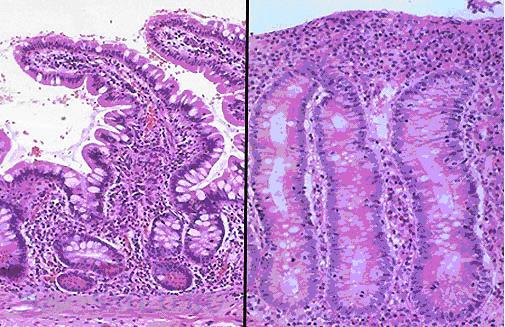

В передней их трети тела расположен присасывательный диск в виде специального углубления. С его помощью лямблии прикрепляются к ворсинкам слизистой оболочки тонкого кишечника. Цитоплазматическая мембрана задней поверхности имеет по краям булавовидные выросты, что также создаёт дополнительную прикрепляющую составляющую.

Патогенность лямблии

Жизнедеятельность этих паразитов сопровождаются выделением во внутренние среды организма человека множество токсинов, что просто отравляет его изнутри. Лямблиоз может сопровождаться нарушениями функций печени, кишечника, желчного пузыря, вызвать некоторые расстройства нервной системы, различные аллергические реакции. Прикрепление лямблий к слизистой оболочке кишечника нарушают ее способность всасывать жиры и углеводы, нарушают пристеночное пищеварение, сказывается на ее секреторной, моторной функции. Большие колонии лямблий могут оказывать вредное механическое воздействие и раздражать эпителий кишечника.